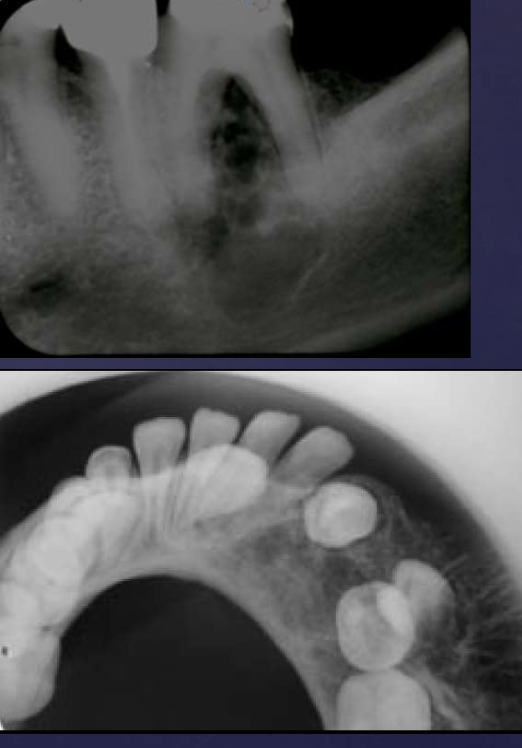

radiographic features of compound odontomas

radiolucent band/soft tissue capsule inside the cortical border

internal content is largely radiopaque: made of tooth-like structures called denticles

maybe associated w/ unerupted tooth

radiographic features of complex odontomas

internal content is largely radiopaque- made of irregular mass of calcified tissue

radiographic features of compound-complex odontomas

mixed density, corticated

combination of amorphous radiopaque mass + tooth-like structures